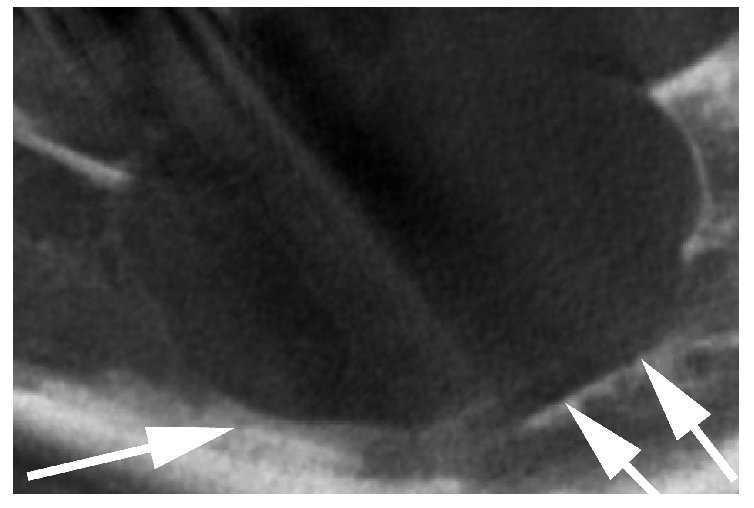

En la tomografía volumétrica digital dental solicitada de forma complementaria se aprecia una masa hipodensa circunscrita con un tamaño de 33 x 18 x 13 mm. El conducto dentario inferior izquierdo está desplazado hacia caudal y lingual (fig. 2). Se observa una apófisis alveolar tumefacta como consecuencia de la masa (fig. 3, flechas negras).

Figura 3. Tomografía volumétrica digital dental, plano coronal.